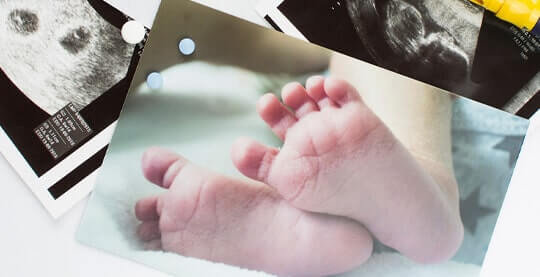

The Veer Hospital is committed to providing affordable, quality health care to patients by incorporating improvement in its day-to-day schedule.

The Veer Hospital provides effective and high-quality healthcare services with 20+ departments, 16 special units and 50+ physicians. We offer an up-to-date medical approach in an ethical and reliable environment. We maintain our reputation in the health sector with our experienced medical staff who continuously improve qualified healthcare with an uncompromising focus when it comes to proficiency and academic values.